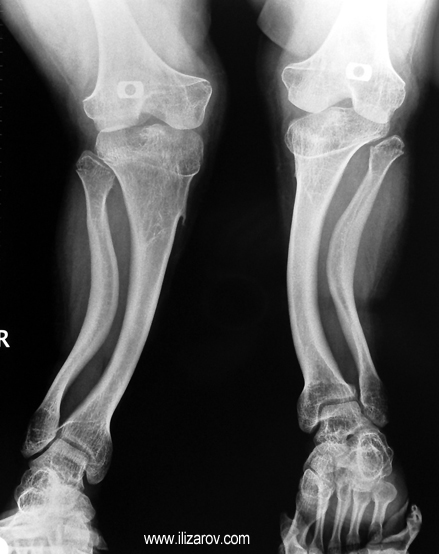

In hypophosohatemic rickets, abnormal bone findings become evident after 1 year of age; there are short stature and deformities around the knee (bilateral genu valgum or varum, tibial torsion, deformity at tibia and femur, ‘windswept’ deformity).

Because the deformity caused by hypophosphatemic rickets is very close to the growth plate, a significant deformity and malalignment occurs. For that reason, more than one deformity centers (CORA) are found at preoperative evaluation, and osteotomy at more than one level is required to correct the deformity. The most frequently used methods to correct the deformity are acute or gradual deformity correction using the Ilizarov method or unilateral external fixator. In the ‘fixator assisted nailing’ technique, which is applied in our department, the deformity is corrected in an acute fashion with the help of an external fixator, and the extremity is stabilized by an intramedullaru nail. The external fixator is removed before the end of the surgery if no gradual lengthening is planned postoperatively. If lengthening (over nail) is planned, the fixator is removed after the completion of the lengthening procedure. As a result, the risk of pin tract infection is eliminated, correction loss and relapsing of the deformity (which are important problems in the treatment of hypophosphatemic rickets) are avoided, eary motion and full weight bearing are allowed, and comfortability of the patient is improved because the duration with external fixator is decreased.